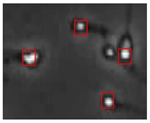

| Case | Conventional Image Processing | YOLOv3-spp | YOLOv5s | YOLOv5s-SA |

|---|---|---|---|---|

| 1 | ![]() | ![]() | ![]() | ![]() |

| 2 | ![]() | ![]() | ![]() | ![]() |